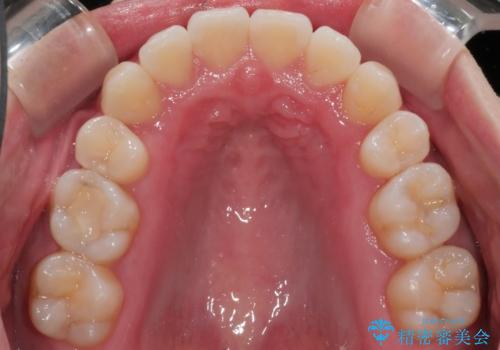

八重歯でがたつきは重度でしたが、きれいな歯並びにすることができました。

がたつきだけでなく、奥歯の噛み合わせのずれの調整もしっかり行いました。

奥歯のずれの調整は時間がかかりますが、矯正後の歯並びの安定度が向上します。

歯並びがきれいになることで、虫歯予防や歯周病予防にもつながります。